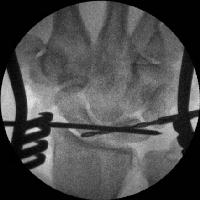

Scapholunate pins and bone anchors - intraoperative fluoroscopy.

Click for larger image